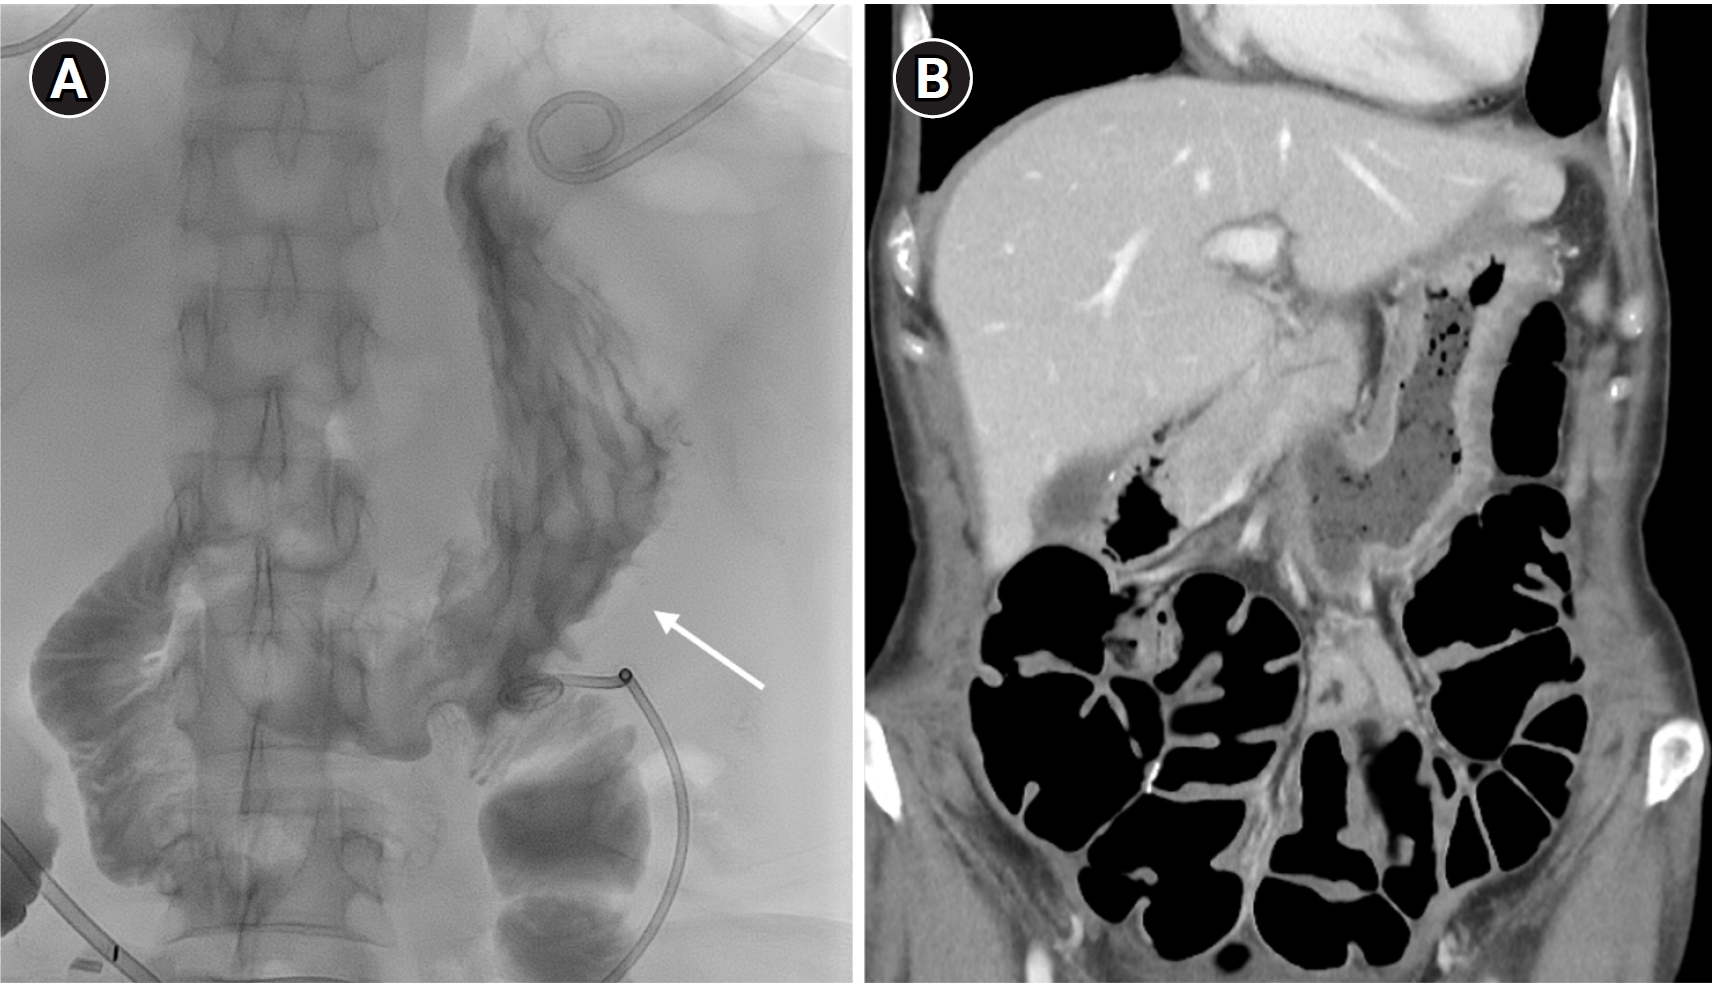

A 53-year-old woman with a history of total abdominal hysterectomy for endometrioid adenocarcinoma 2 years earlier and subsequent adjuvant chemoradiation therapy presented with adhesive ileus. She underwent adhesiolysis and small bowel resection; however, the surgery was complicated by anastomotic leakage, resulting in the formation of multifocal intraperitoneal abscesses. The perigastric abscess (

Fig. 1A) was accessed under ultrasonographic and fluoroscopic guidance. The following day, CT showed an 8.5-French PCD catheter located within the stomach (

Fig. 1B).

Fig. 1.A 53-year-old woman with a history of adhesiolysis for ileus presented with fever and abdominal pain. (A) Axial CT image shows multiloculated intraperitoneal fluid collections requiring drainage (asterisks). (B) Coronal CT image shows a percutaneous drainage catheter inadvertently placed within the stomach (arrows).